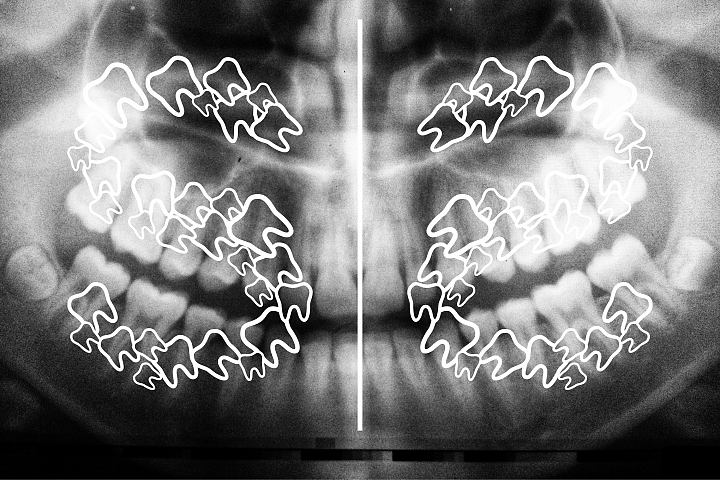

Understanding Teeth Numbers: A Visual Guide - Take Home Smile

takehomesmile.com999 Mẫu Dental Desktop Backgrounds Chất Lượng HD, Tải Ngay

takehomesmile.com999 Mẫu Dental Desktop Backgrounds Chất Lượng HD, Tải Ngay